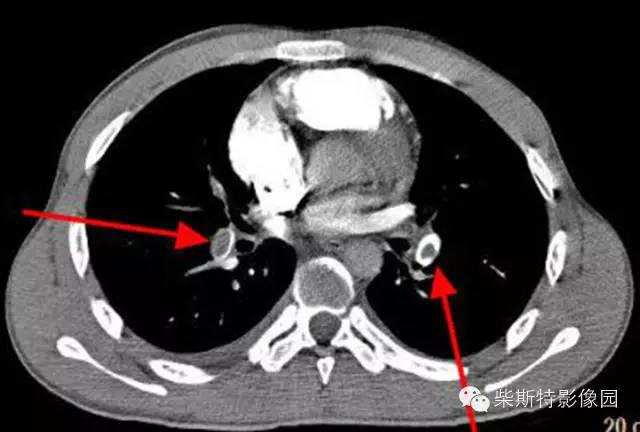

第二大名捕:肺动脉CTA

红色箭头所指处即栓塞导致的充盈缺损,从横断位、冠状位、矢状位三个层面观察,造影剂为高密度白色,而栓子的存在导致造影剂无法充填,从而表现为黑色的低密度影。俗话说的好:长江后浪推前浪!肺动脉CTA的本领已经基本超越其“大哥”肺动脉造影!还可以估测房室大小!